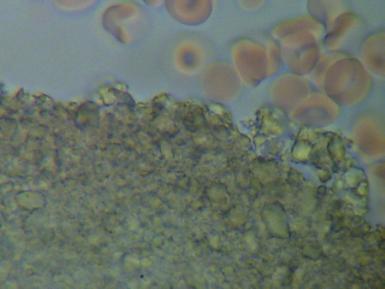

2.PASOŻYTY I GRZYBY

w zakwaszonym środowisku rozwijają się różnego rodzaju organizmy pasożytujące : robaki, grzyby, bakterie, wirusy i inne. Walka z nimi jest możliwa tylko przez zmianę środowiska z kwaśnego na zasadowe, w tym środowisku nie mogą się one rozmnażać i żyć.

We krwi widoczne są larwy i jaja pasożytów.

Komórki grzybów. W zależności od tego w jakim stopniu organizm zaatakowany jest przez grzyba widoczny jest obraz pojedynczych komórek lub całych kolonii i wtedy możemy mówić o bardzo niebezpiecznej dla organizmu grzybicy.